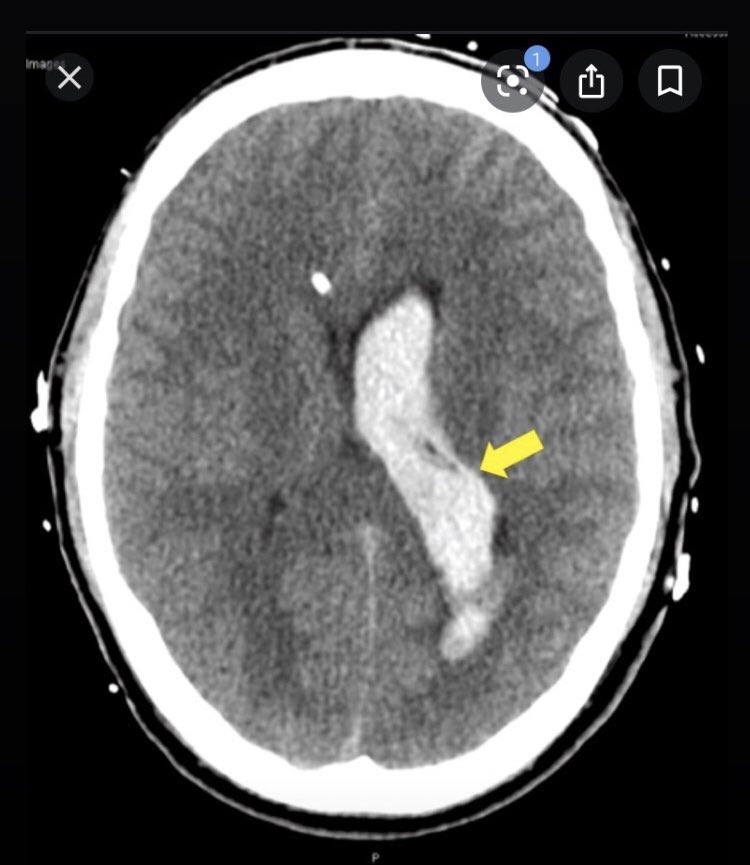

اخر حالة: رجل دخل بنوبة قلبية قبل يومين فجأة توقف عن الرد لما الممرضة حاولت تتحدث معه. ما بيرد بس بيتنفس عادي وبؤبؤ عينه اليسار متوسع على الفحص بس عينه اليمين لأ

شو صار معه؟

(هذه حالات حقيقية لكن الصور من جوجل للتوضيح)